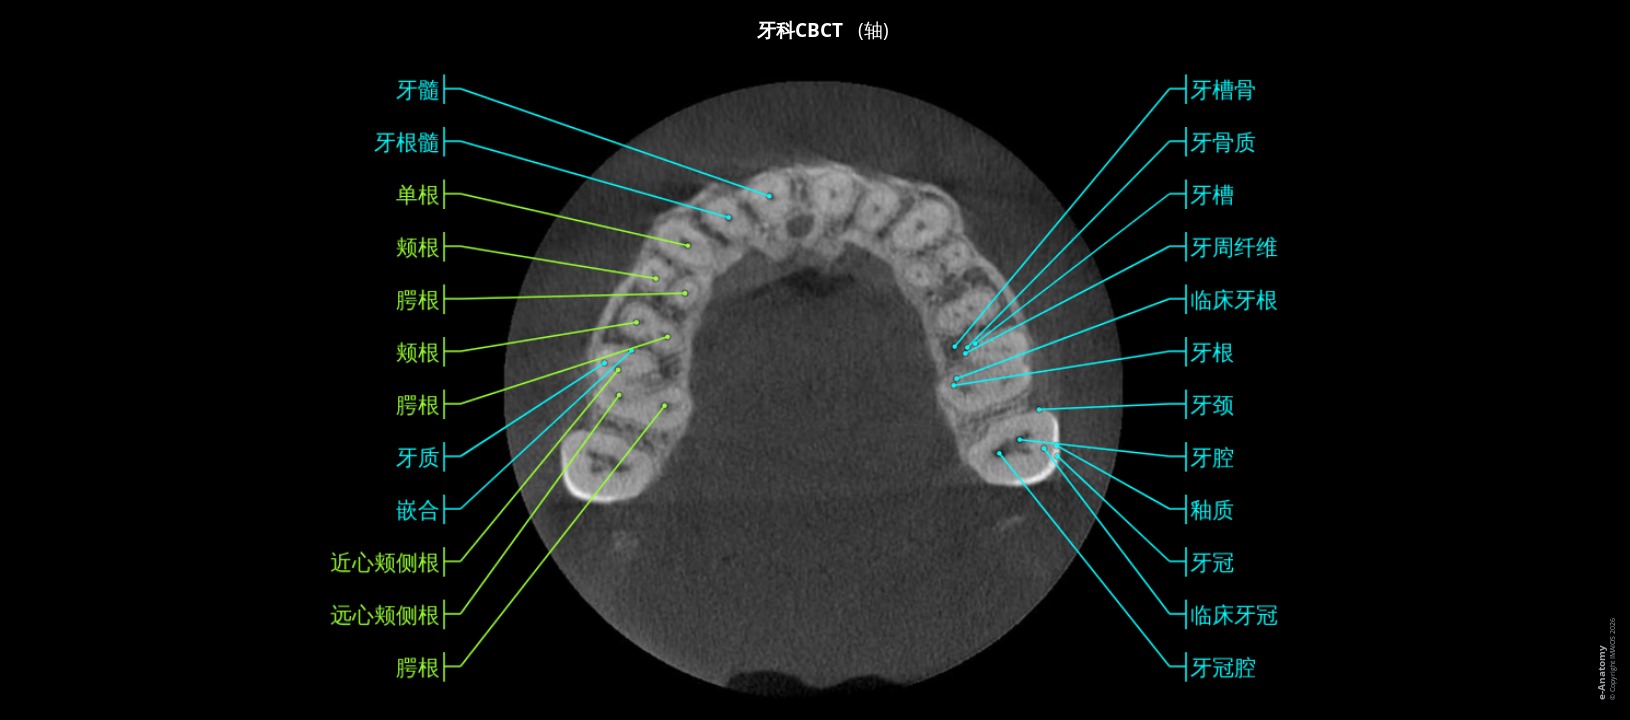

注意!此项检查缺少上颌和下颌第三磨牙。

牙科锥形束计算机断层扫描 (CBCT) 检查已被广泛接受,可用于几乎所有牙科领域的临床应用。

牙科CBCT允许牙科专家(牙医、口腔颌面外科、人工植牙和牙髓病学):

- 评估底层骨骼结构,以及神经通路和周围软组织

- 显示潜在的牙齿问题,例如蛀牙、骨质流失、异常生长、面部骨折、牙周感染、颞下颌关节不规则以及牙根或牙髓问题。

- 计划人工植牙。

- 提供准确的测量值,包括下颌骨的形状和尺寸。

- 识别牙龈问题。

- 评估鼻窦和鼻腔。

此牙科CBCT由Antoine Micheau医学博士(法国蒙彼利埃放射科医生)使用 ProMax 3D Planmeca对一名男性患者进行。

可惜的是上颌和下颌第三磨牙缺失(小时候第三磨牙被移除)。

根据日常生活中最常用的那些选择成像平面和重建:正交(横向)、矢状和正面平面、带有牙齿横截面的弯曲MPR重建和全景(正断层摄影)重建、骨结构的三维容积透视。

解剖结构是由Antoine Micheau医学博士(法国蒙彼利埃放射科医师)根据Terminologia Anatomica 1所标记的。